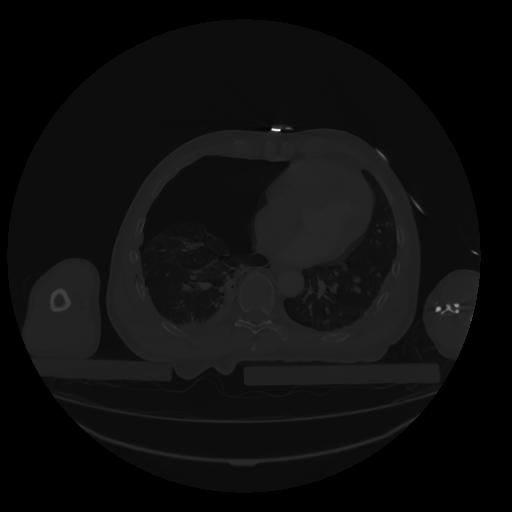

28 CUERPO,CE,Vol,2.0,CUERPO,,